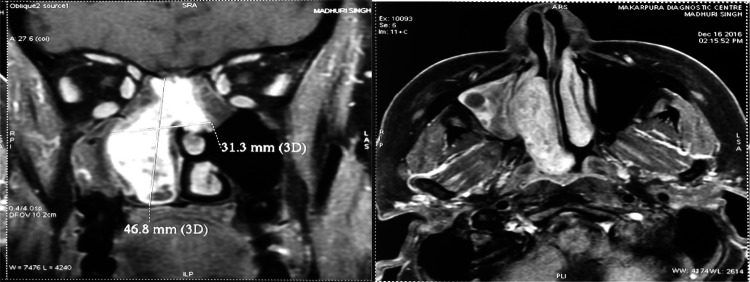

A 41-year-old female was admitted in our Department in December 2016 for right chronic nasal obstruction and bleeding [epistaxis]. A contrast CT scan showed heterogeneously enhancing dumbbell shaped lesion measuring 4.8 cm × 4.6 cm × 1.7 cm [AP X CC X T] involving right maxillary antrum extending through ostium in right nasal cavity, right middle turbinate -meatus and abutting right inferior turbinate posteriorly and just protruding in post nasal space with changes of post-obstructive sinusitis in bilateral ethmoidal and right sphenoid sinus. No intraorbital and intracranial extension was seen. Biopsy was taken from the mass following which the nose had to be packed to control bleeding. Histopathological examination revealed Hemangiopericytoma. MRI of brain was done to reveal any oblivious soft tissue/ intracranial extensions. It showed a well defined expansile heterogeneously enhancing solid mass lesion in right nasal cavity with ethmoid sinuses involvement. There was focal destruction of posterior-superior nasal septum and extension of lesion into left posterior ethmoid sinus and nasopharynx. Right middle turbinate was not visualized separately from lesion and right inferior turbinate was compressed. There was no intraorbital and intracranial extension (Fig. 5).

A 40-year-old male was admitted in our Department in march 2016 for left chronic nasal obstruction and left nasal cavity bleeding. CT PNS with contrast showed ill defined enhancing soft tissue density lesion measuring 4.6 cm × 5 cm × 2.2 cm [AP X CC X T] involving left nasal cavity, ipsilateral ethmoid sinus and projecting into left frontal sinus with destruction of adjacent bony nasal septum was seen. Contralateral extension was seen involving right nasal cavity and abutting right middle turbinate. Erosion of medial wall of left orbit and bony walls of left frontal sinus was seen. There was destruction of left cribriform plate with mild intracranial extension of lesion abutting left frontal lobe (Fig. 6).

Fig. 6.

CT PNS showing soft tissue density lesion of left nasal cavity, left ethmoid sinus and projecting into left frontal sinus with destruction of adjacent bony nasal septum